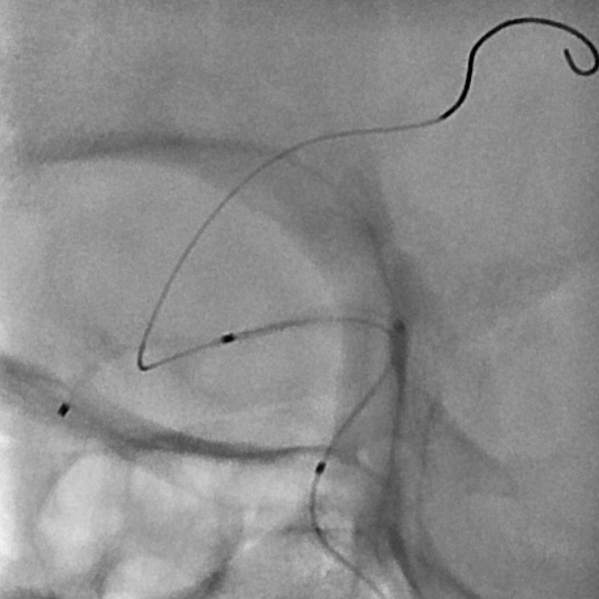

粗大分支从破裂瘤体上发出来,急性期能单纯致密栓塞吗?

病史:中年女性,新冠感染,颅内动脉瘤破裂,Hunt-Hess 4级